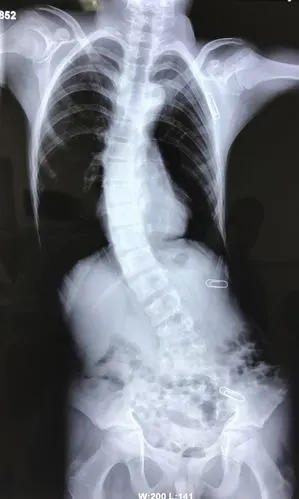

腰椎滑脱伴脊柱侧弯一例